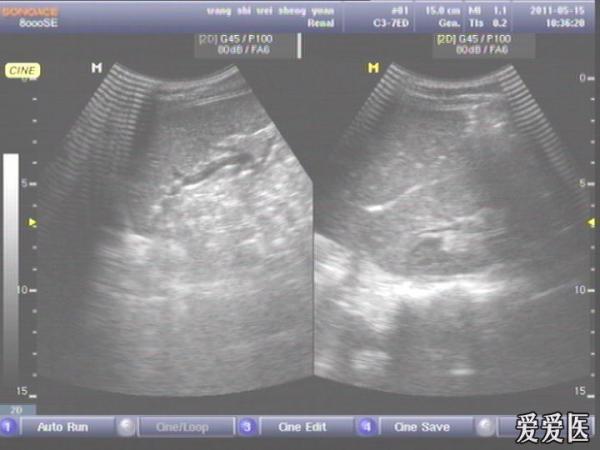

患者,男,38岁,进食后突发上腹部持续性剧烈疼痛一小时来查。超声见横膈与肝之间、上腹部皮下气体强反射回声,后伴多重反射,肝前、肝肾间隙,腹腔肠管间均可见游离无回声区。直视腹部见上腹部似板样。结合病史提示“胃肠道穿孔”。急诊手术证实。